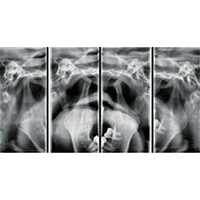

ATM